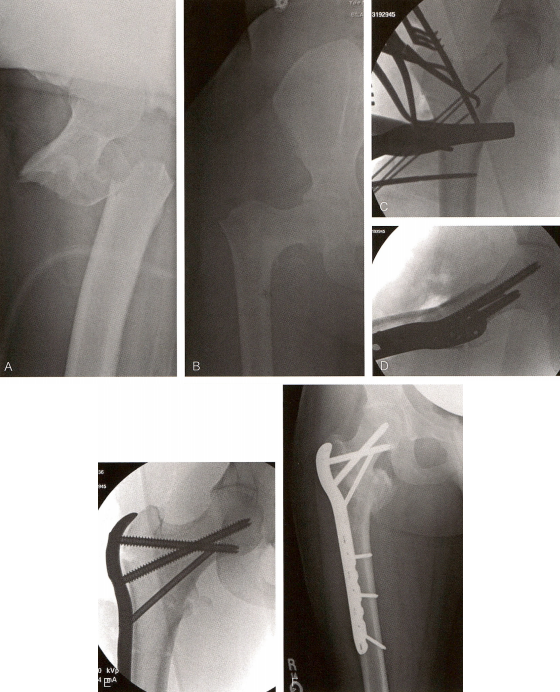

当股骨外侧和转子间显露后,若采用直接复位,可借助点式复位钳、克氏针或拉力螺钉将转子间骨块对合于股骨(技术图4)。如果采用间接复位,则要确保刃钢板置人近端头颈骨块的位置正确,这样在刃钢板远端逐渐贴近骨干时骨折将得到复位。骨块复位后打人导针,方便骨凿给刃钢板精确开口。**枚导针放置于股骨颈前皮质表面,钻进股骨头的前部,标示股骨的前倾角。在透视或角度导向器的引导下,沿大转子顶点,与股骨干成90°角,朝向股骨头打人第二枚导针。在第二枚导针稍远侧,平行于两枚导针插人骨凿,注意骨凿与股骨干保持正确对线,因为这决定了骨折端在矢状位的屈伸对位关系,该关系在刃钢板置入后就固定了。骨凿要通过股骨颈的中部,固定于股骨头的下部。由于股骨头的解剖位置相对于股骨干存在前移,要让钢板通过前述位置,转子间的骨凿开口处要位于其前半部分。骨凿的位置在打入全程都要借助透视反复确认。

图片

技术图4 置入刃钢板。A、B.一例28岁男性31-A3型骨折患者的术前正侧位片。C.采用拉力螺钉将股骨头、股骨颈和转子间固定为一整块后打入骨凿。D.插入刃钢板。E.术后正位片。

小心移除骨凿,置入合适长度的刃钢板,将其轻柔地固定于近端骨块。双平面透视反复确认刃钢板沿着预凿的通道置人。刃钢板插入后,最近端的螺孔打人一枚双皮质螺钉,拉住股骨颈的内侧皮质,确保钢板与近端骨块坚强固定。将钢板压向股骨干时会带着近端骨块一起实现骨折复位,该过程还要同时注意恢复长度和控制旋转。若有需要,可使用股骨牵开器来辅助复位。牵开器需固定于股骨外侧,近端钉打入头颈骨块,远端钉位于钢板远端的股骨骨质。跨骨折区牵开,通过周围软组织的牵张来改善骨折端的对位和肢体长度。用一把复位钳轻柔地夹住远端骨块和钢板,防止牵开时骨折内翻。使用点式复位钳复位粉碎骨块,并避免剥离其软组织附着。透视确认骨折复位。若骨折对位尚可接受,撤去牵开器,使得骨块位置彼此靠近实现加压。而后采用标准置钉技术将钢板固定于骨干,此前放置点式复位钳处置入拉力螺钉固定。透视确认骨折最终的对位、长度的恢复,并确保内植物未穿出股骨头。